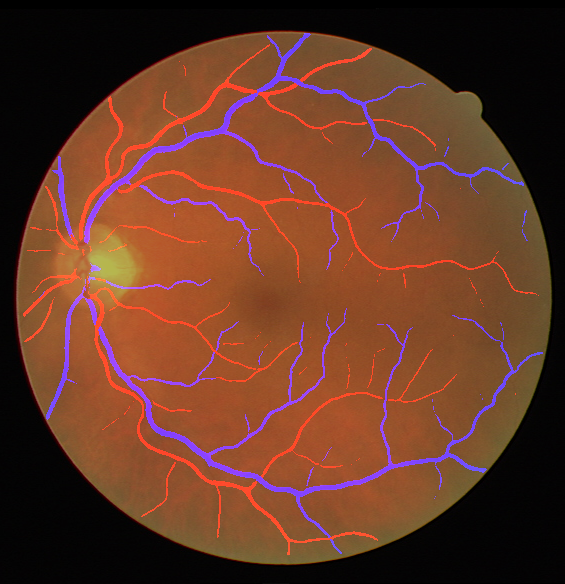

Using the final pretrained student SegRAVIR model in our knowledge distillation framework described in Section IV-D, we fine-tuned and tested the network on three publicly available datasets of color images, DRIVE [10], STARE [9], and CHASE_DB1 [12]. Fig. 7 shows example of SegRAVIR segmentation outputs on DRIVE and CHASE_DB1 datasets. Table VII presents a quantitative comparison between the segmentation performance of our SegRAVIR model and state-of-the-art models: R2U-Net [25], DU-Net [26], and IterNet [34]. By all evaluation metrics, SegRAVIR has achieved new state-of-the-art results on the DRIVE, STARE [9], and CHASE_DB1 datasets.